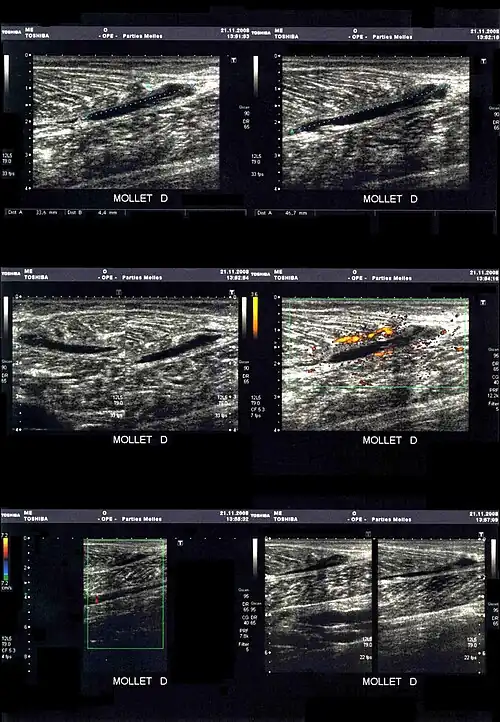

La déchirure apparait sous la forme d'une zone hypoéchogène (sans écho, et donc noire).

En cas de doute ou pour préciser les dégâts musculaires dans les cas les plus graves, une déchirure peut être mise en évidence par l'imagerie médicale[15] :

- échographie/échotomographie : « examen le plus utile et le moins cher, permet une étude des fibres musculaires, des tendons et des aponévroses. Ses limitations sont la mauvaise analyse des zones profondes, comme l’insertion proximale des ischio-jambiers, et la difficulté à détecter parfois les cicatrices »[3].

- IRM : plus coûteuse, elle est aussi plus sensible, sans toutefois permettre d’étudier directement les fibres musculaires[16]. Elle est utilisée en cas d'insuffisance de diagnostic par échographie (en deuxième intention)[3].